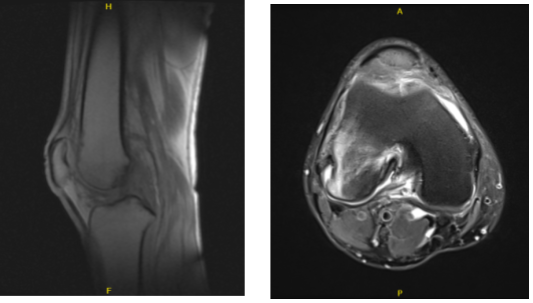

An MRI revealed a medial meniscus rupture, subcondylar fracture, and microfracture of the lateral femoral condyle. The patient’s lateral femoral condyle was extremely painful. The patient was not weight bearing and so received no benefit.

MRI-3T Right knee non-contrast